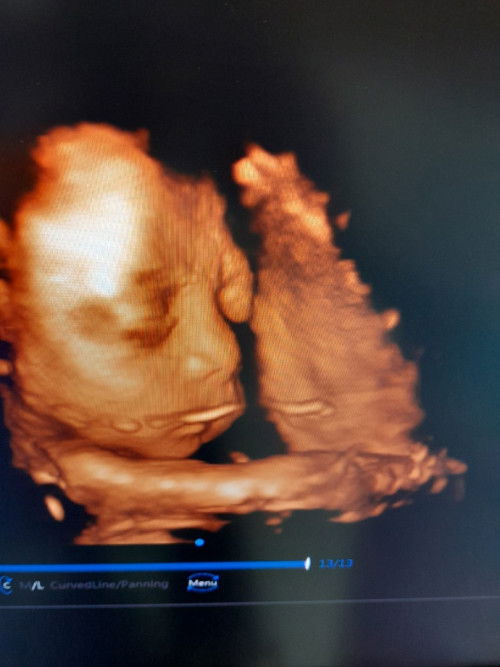

33 สัปดาห์แล้ว นอนลำบากมากเลยท้องแข็งถี่ตลอด #ลูกชาย